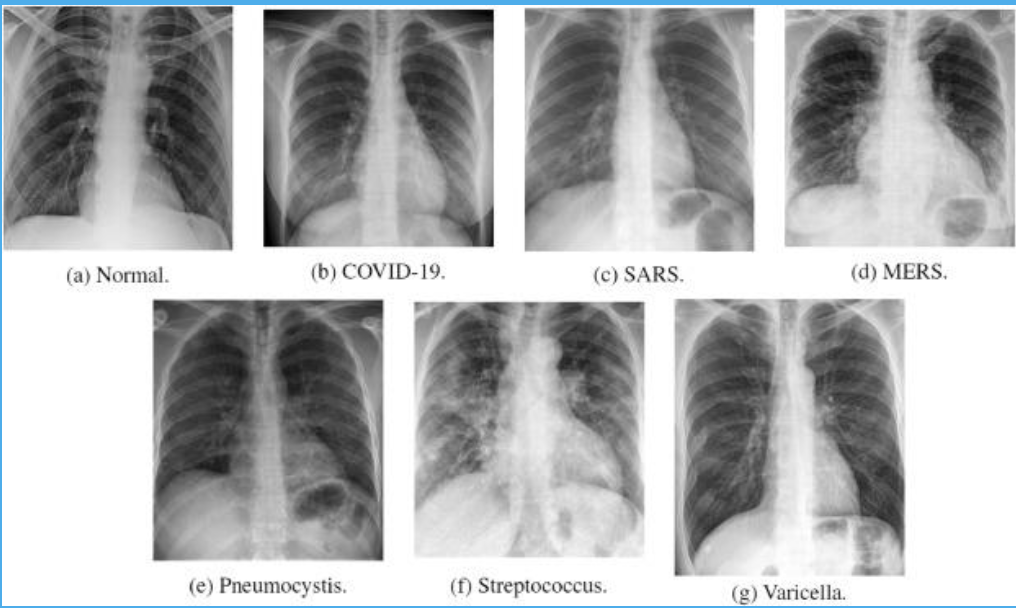

• Preprocessing chest X-ray datasets for training deep learning models.

• Sourced chest X-ray datasets from medical repositories.

• Resized images (512x512, 256x256 pixels) to optimize training.

• Applied data augmentation to improve generalization.